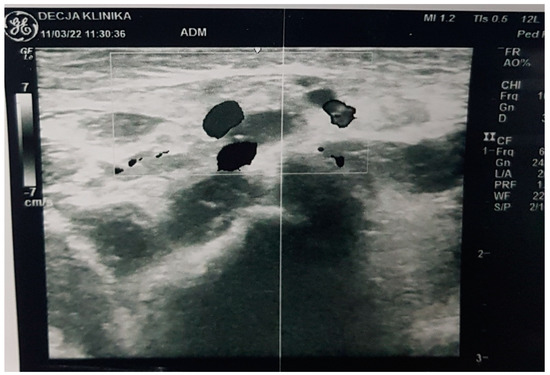

| Clinical picture at admission in Pediatric Clinic UCC | NN1 had a preserved sensorium, was high febrile 39.4 °C (rectal), with tachy-dyspnea, sobs, and moans, indents jugulum, dissatisfied cries, TM 4050 g, subclinical jaundice of the skin, and visible mucosa. Auscultation revealed attenuated respiratory sound, diffusely fine crackles, SaO2 82%, R 56/min, F 196/min. The umbilical stump persisted, the surrounding skin became red and swollen, there was hypotonia of the body axis, large fontanelle within the bony borders, greatness 20 × 30 mm. The other physical findings were normal. | NN2 had the preserved sensorium, was afebrile 37.7 °C (rectal), TM 3920 g, eupnoeic, presented sobs and moans, plethoric and icteric skin, nasal vestibules filled with seromucous secretion, and hyperemic throat. Auscultatory revealed a normal breathing sound is heard with transmitted wheezes from the upper parts of the airways and systolic murmur of 1-2/6 according to Levin, SaO2 97%, R 32/min, F 168/min. The umbilical stump persisted, thin, and the borders developed a serous–hemorrhagic discharge. There was mild hypotonia of the shoulder girdle and trunk axis, primitive reflexes were slowly elicited, large fontanelle was below the plane of the bony borders, and slightly spaced sutures, greatness 40 × 40 mm. The other physical findings were normal. |